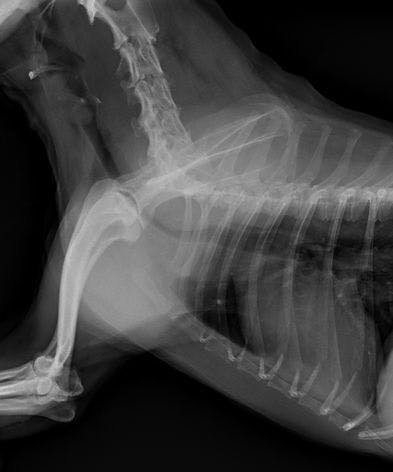

6歳のポメラニアン【こつぶ】が気管虚脱を患っております。

「グレード4」で気道の90%以上が潰れてしまっている状況です。

気管虚脱は、気管の狭窄の度合により4段階に分類されます。一番症状の軽い「グレード1」では25%以下の気管の狭窄、最も進行している「グレード4」では75%以上の狭窄となります。

虚脱の初期病変は、90%以上が頚部気管で、進行するにしたがい胸部気管、さらには気管支へと潰れる範囲が広がっていきます。